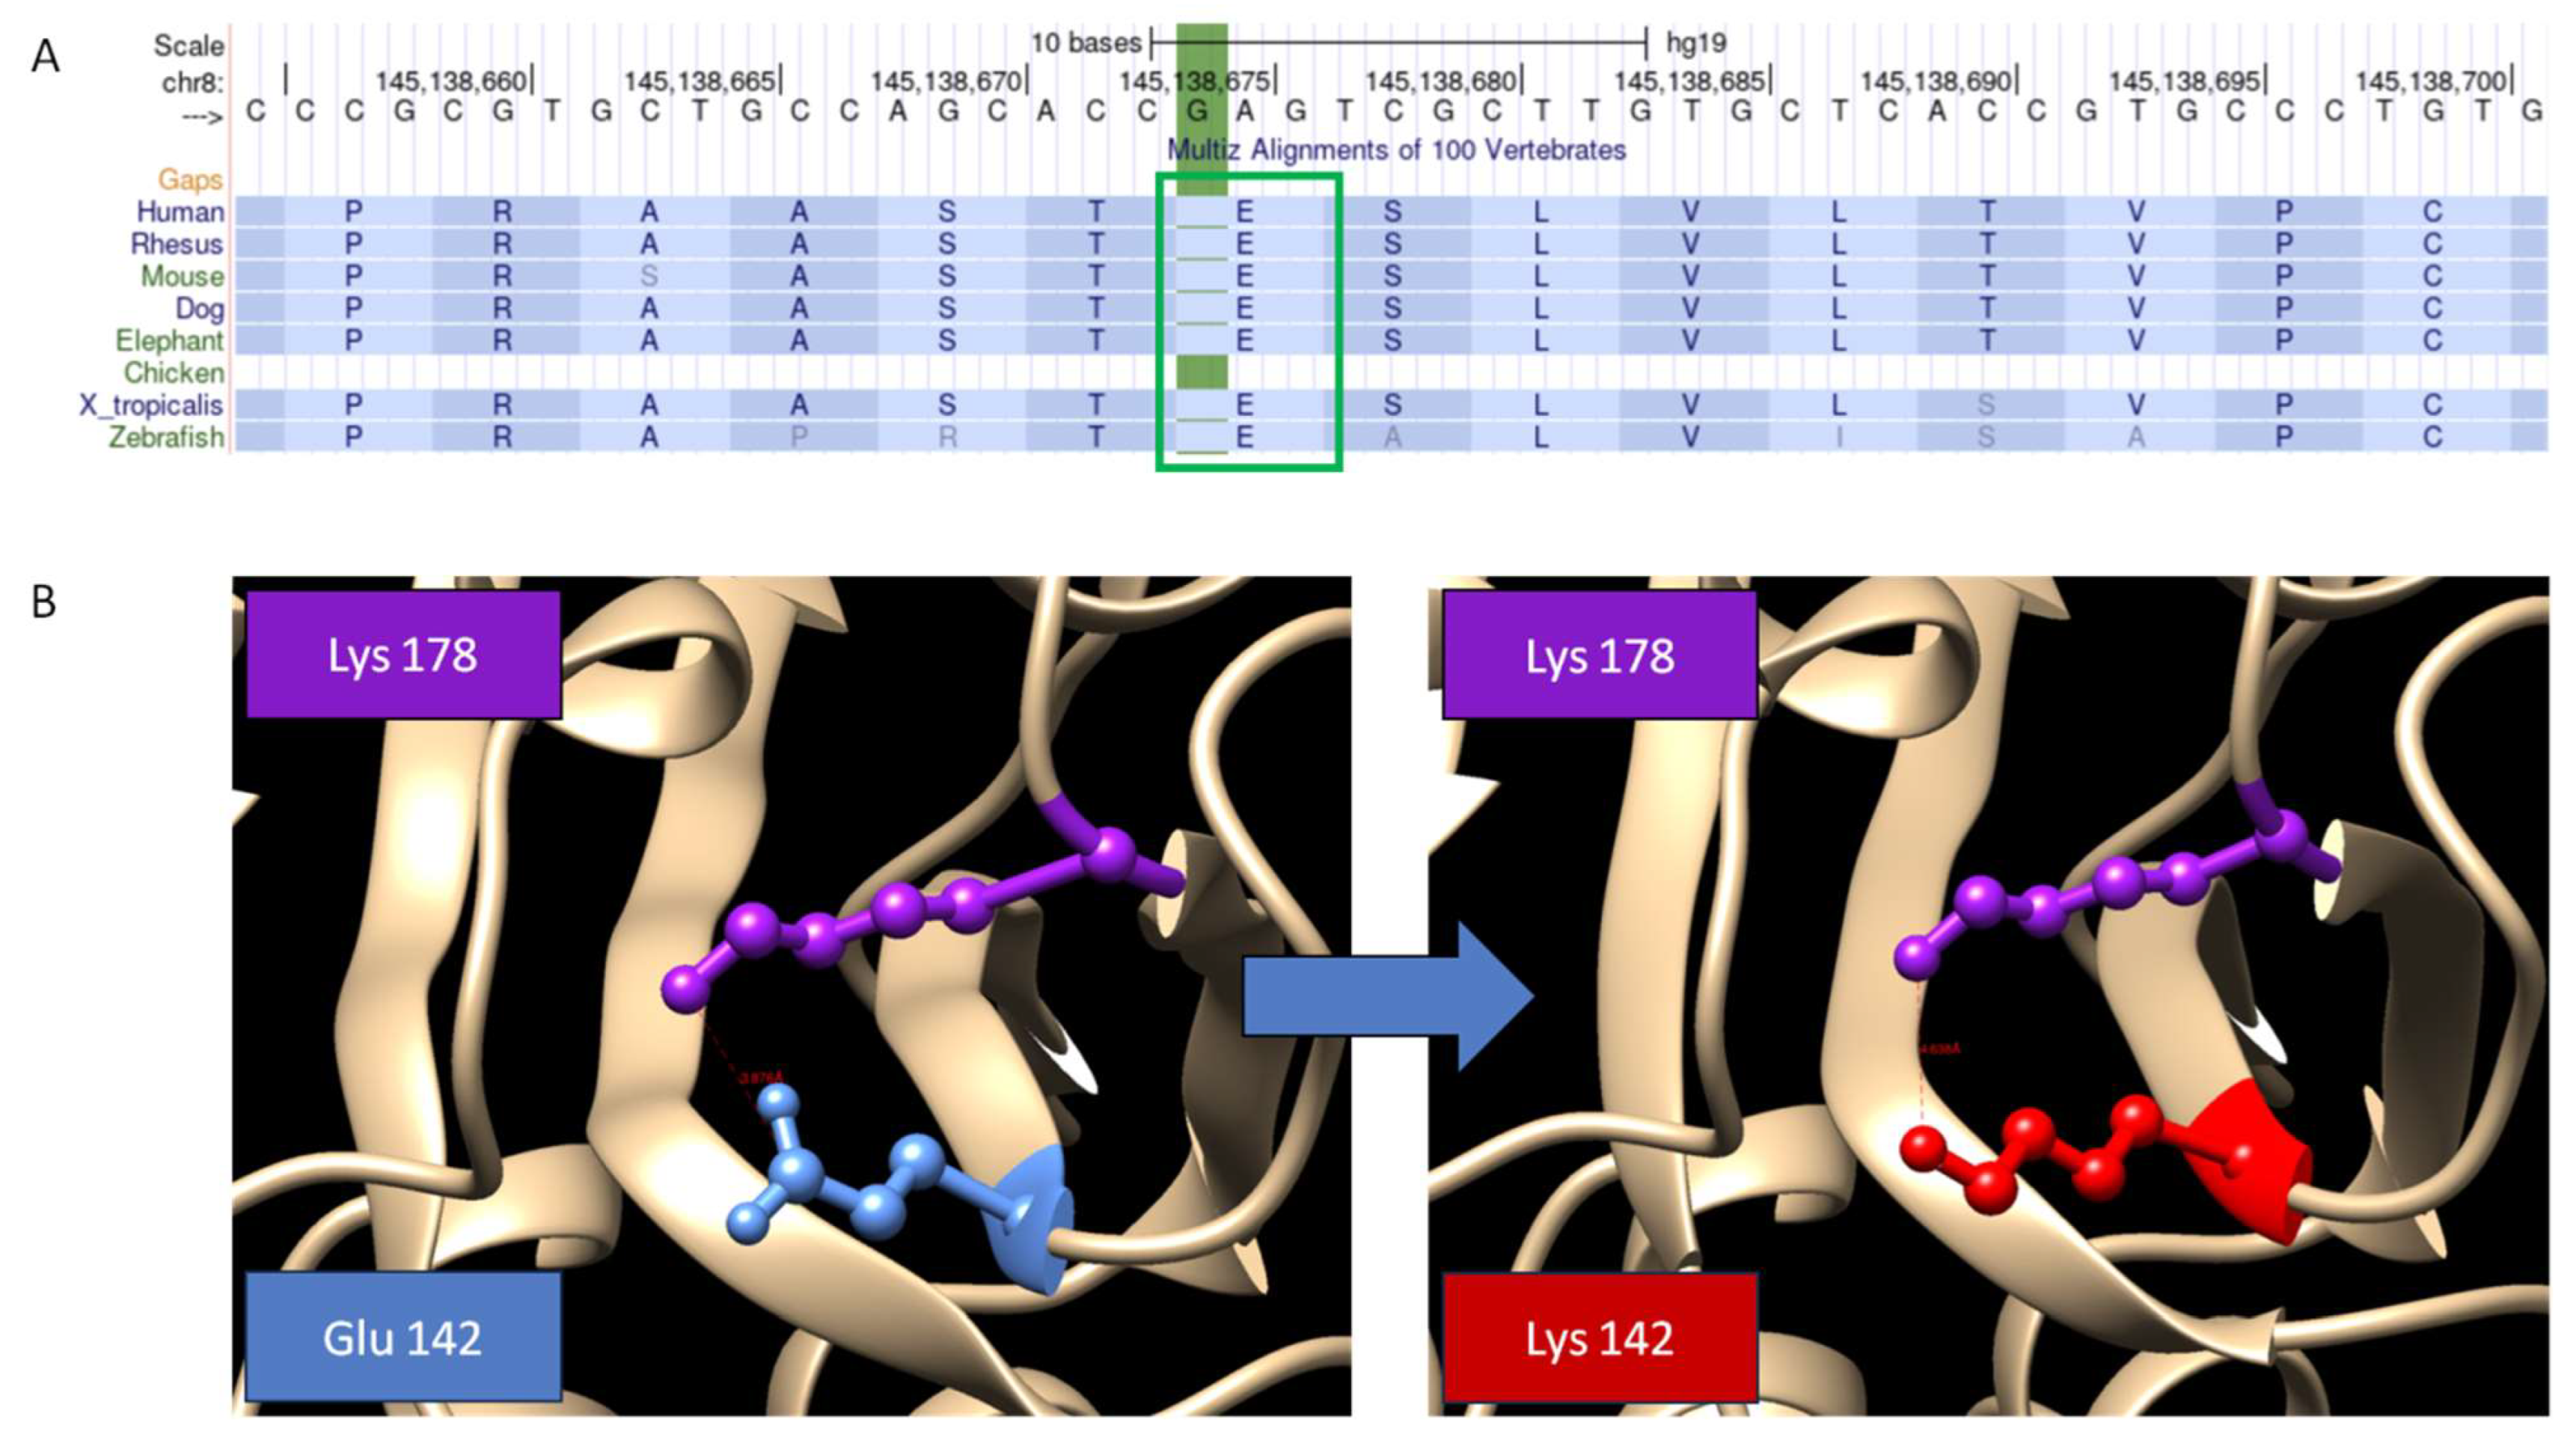

4. Results

5. Discussion